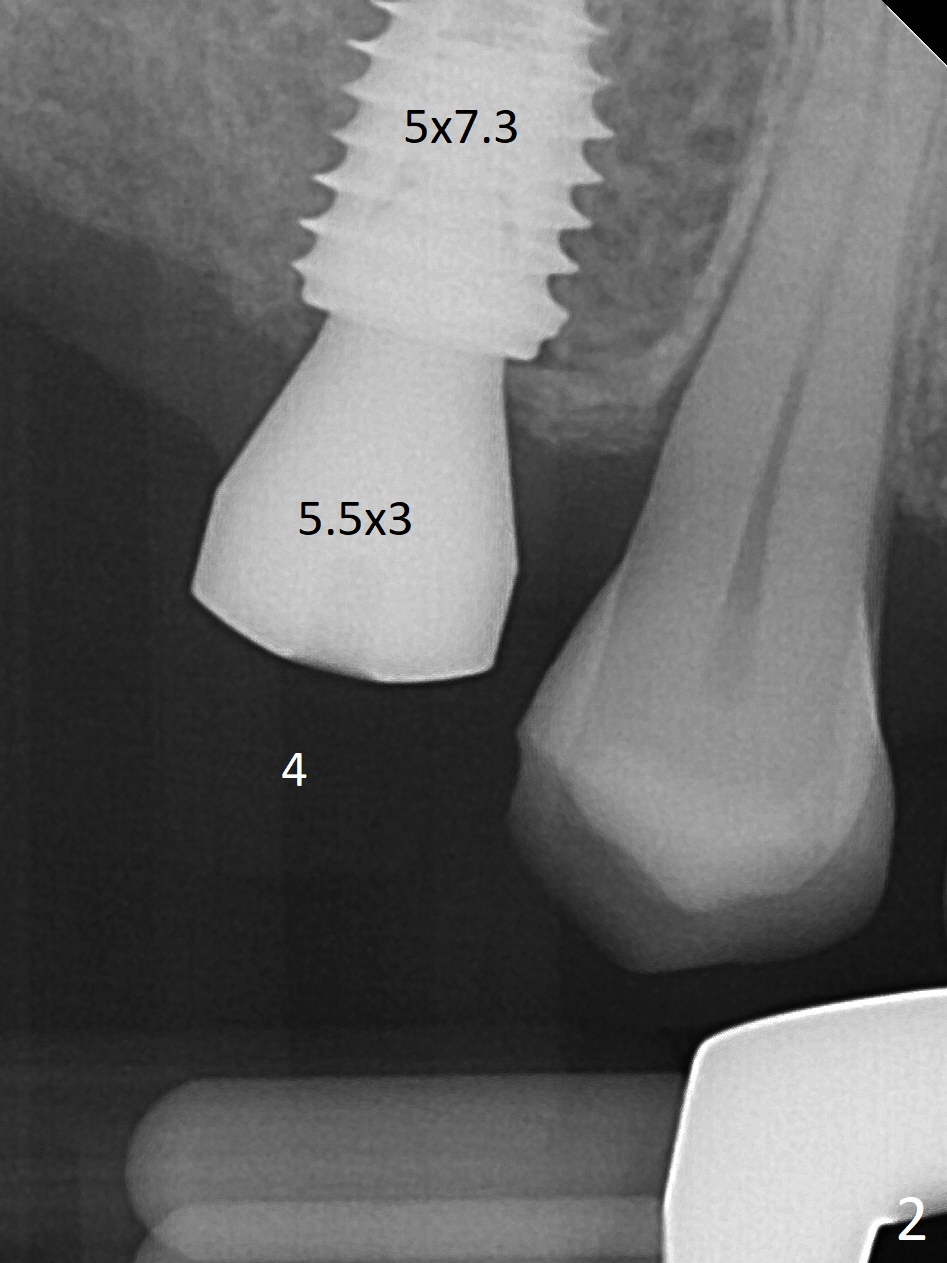

Eight months post socket preservation, the bone density at #2 feels low during osteotomy.  The site is underprep not only in depth, but also in diameter (4.0x7.3 mm with 10.5 mm offset), but a 5x7.3 mm implant is ~ 1 mm shy of the purposed depth.  Following 4.5x7.3 and 4.0x8.5 mm drills (without air leak), the implant reaches the depth, but with ~ 5 Ncm insertion torque (Fig.1).  Placement of the same sized implant at #4 (healed site) is smooth with satisfactory stability (~30 Ncm, Fig.2,3).  Ideally the site of #2 should have been prepared with sinus lift so that the apex of a longer implant would be engaged to the sinus floor for stability.  These two implants heal normally clinically and radiographically 1.5 months postop (Fig.4-6).  Bone surrounds the implant at #2 when it is uncovered 4 months postop (Fig.7).  The retainer at #4 looks short with large gingival embrasure (Fig.8 *) 6.5 months postop.  Finally the patient is ok with it because she does not like gingivectomy.  Provisional should have fabricated (Fig.9 light yellow curved lines) to create gingival scallops with secondary formation of papillae (arrows).